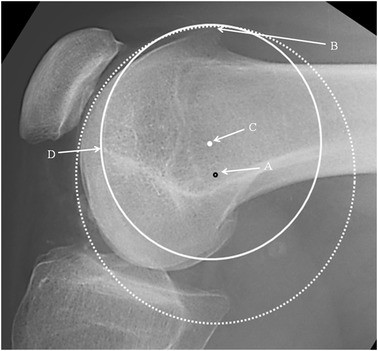

It was noticeable that when applying a circle to the groove line in the PFI cohort, the circle could be placed to touch two points on the groove, e.g., B and D (Fig. 3) or the circle could match much of the groove (Fig. 4). In the control cohort the groove matched a circle. In Fig. 3, for a patient with TD, it can be seen that the isometric point is anterior to Schöttle’s point, and the radius of the circle from Schöttle’s point to the apex of the boss is longer than that for the best-fit circle. This would result in a significantly anisometric graft if the Schöttle’s point was used as the femoral tunnel position. In Fig. 4, in TD, isometric point moves anteriorly as the circle is made smaller. This implies that there is potential for significant error in the isometric point position in TD. A much more complex methodology is needed requiring 3D reconstruction and analysis of the tracking of the patella to define the femoral tunnel position in the presence of TD. This is not appropriate for the surgeon in a clinic. Interestingly, using 3D CT scans in different degrees of knee flexion, Blatter et al. [4] only found one isometric point in 10 normal knees when measuring the MPFL length with a maximal length difference during knee flexion of 10 mm. They also noted that for most, the optimal tunnel position was slightly anterior to Schöttle’s point. It would be interesting to know how this correlated with the lateral plain radiograph.

Lateral radiograph of the knee showing: Schöttle’s point: black rimmed spot (A). Isometric point: white spot (C). Dotted circle: centred on Schöttle’s point with the radius to the highest point of the boss (B). Complete circle: centred on the isometric point. Note that the dysplastic groove is not an arc of this circle. Point D is the distal end of the notch